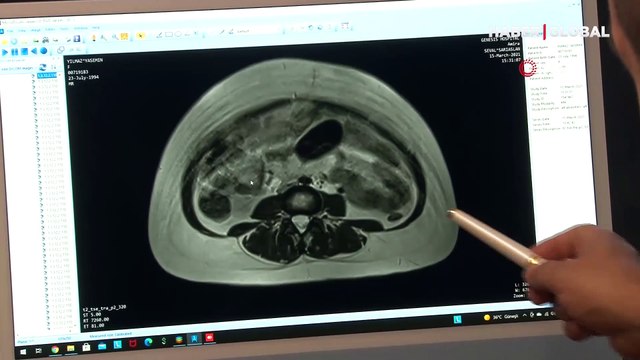

Yıllardır karnı şiş geziyordu, doktora gidince gerçeği öğrendi Şişkinlik yaşayan kadının karnından, 9 aylık bebeğin boyutunda ulaşan kist çıkarıldı Genel Cerrahi Uzmanı Op. Dr. Yıllardır karnı şiş geziyordu, doktora gidince gerçeği öğrendi Şişkinlik yaşayan kadının karnından, 9 aylık bebeğin boyutunda ulaşan kist çıkarıldı Genel Cerrahi Uzmanı Op. Dr. İhsan Oruk: Kistin içinden ortalama 2 buçuk litre iltihap boşalttık Hasta Yasemin Yılmaz: Geceleri hareket ediyordu ESKİŞEHİR - Geceleri yatarken vücudunun içerisinde hareketlilik olduğunu fark ederek doktora başvuran 27 yaşındaki Yasemin Yılmaz'ın karnından, neredeyse 9 aylık bebek boyutuna ulaşan 2 buçuk kilogramlık kist çıkarıldı. Diyarbakır'da yaşayan İngilizce öğretmeni Yasemin Yılmaz, küçük yaşlardan beri karnında oluşan şişliğin genetik veya yedikleriyle bağlantılı olduğunu düşünerek yaşıyordu. Haber</a> haberler.com/yillardir-karni-sis-geziyordu-doktora-gidince-14351453-haberi/